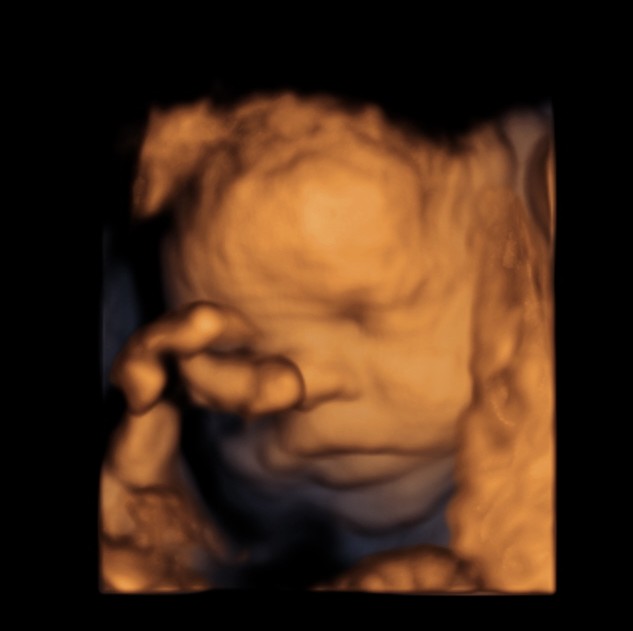

BABY FACE ( Just for fun ) Date: May 25, 2014Author: kriznan Category: 3 d images, fetal face, Fetal Ultrasound, ultrasound images Tags: baby face 3 d images, baby sucking finger, baby yawning Post navigation ← HEMANGIOMA OF THE LIVER IUGR OR SKELETAL DYSPLASIA OR RENAL DYSPLASIA → This is just an intermediate filler . enjoy the expressions. Thinking Yawning or just putting out the tongue Sucking the fingers Wondering So , what is lost now ? ok Papparazi ! enough for the day . go away. Share this: Share on X (Opens in new window) X Share on Facebook (Opens in new window) Facebook Email a link to a friend (Opens in new window) Email Share on LinkedIn (Opens in new window) LinkedIn Share on WhatsApp (Opens in new window) WhatsApp More Print (Opens in new window) Print Share on Reddit (Opens in new window) Reddit Share on Tumblr (Opens in new window) Tumblr Share on Pinterest (Opens in new window) Pinterest Share on Telegram (Opens in new window) Telegram Like Loading...